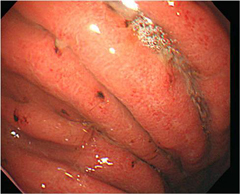

¿ª·ù¼º½Äµµ¿°ÀÇ ³»½Ã°æ »çÁø

À§½Äµµ ¿ª·ùÁúȯ?

À§·Î ³»·Á°£ À½½Ä¹°ÀÌ ´Ù½Ã ½Äµµ·Î ¿Ã¶ó¿À´Â Áõ»óÀ¸·Î °¡½¿ºÎÀ§°¡ ¾²¸®°í ½Å¹°ÀÌ ¿Ã¶ó¿Â´Ù. ½Ä»ç ÈÄ ÁÖ·Î ´À³¢°Ô µÇ°í, ±â¸§Áø À½½ÄÀ» ¸ÔÀ¸¸é Áõ¼¼°¡ ½ÉÇØÁø´Ù.